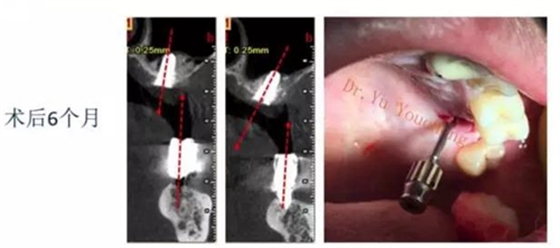

系列課開(kāi)播前小編為大家預(yù)告了一例上頜竇外提升術(shù)后種植體方向改變的病例,當(dāng)時(shí)頓生種種疑惑:“真的么?怎么會(huì)?怎么辦!!”在本次課程中余教授給出了答案:上頜竇外提升同期種植有一重要的因素,即種植體初期穩(wěn)定性的獲得。該患者由于其骨量的嚴(yán)重不足,雖然可通過(guò)大直徑覆蓋螺絲保證種植體不至于滑落,但隨著竇粘膜的運(yùn)動(dòng)和部分移植骨的吸收,種植體方向最終受到了影響,這也提示我們?cè)谥贫ㄖ委熡?jì)劃過(guò)程中應(yīng)慎重考慮這一因素,以確保更好的種植預(yù)后效果。